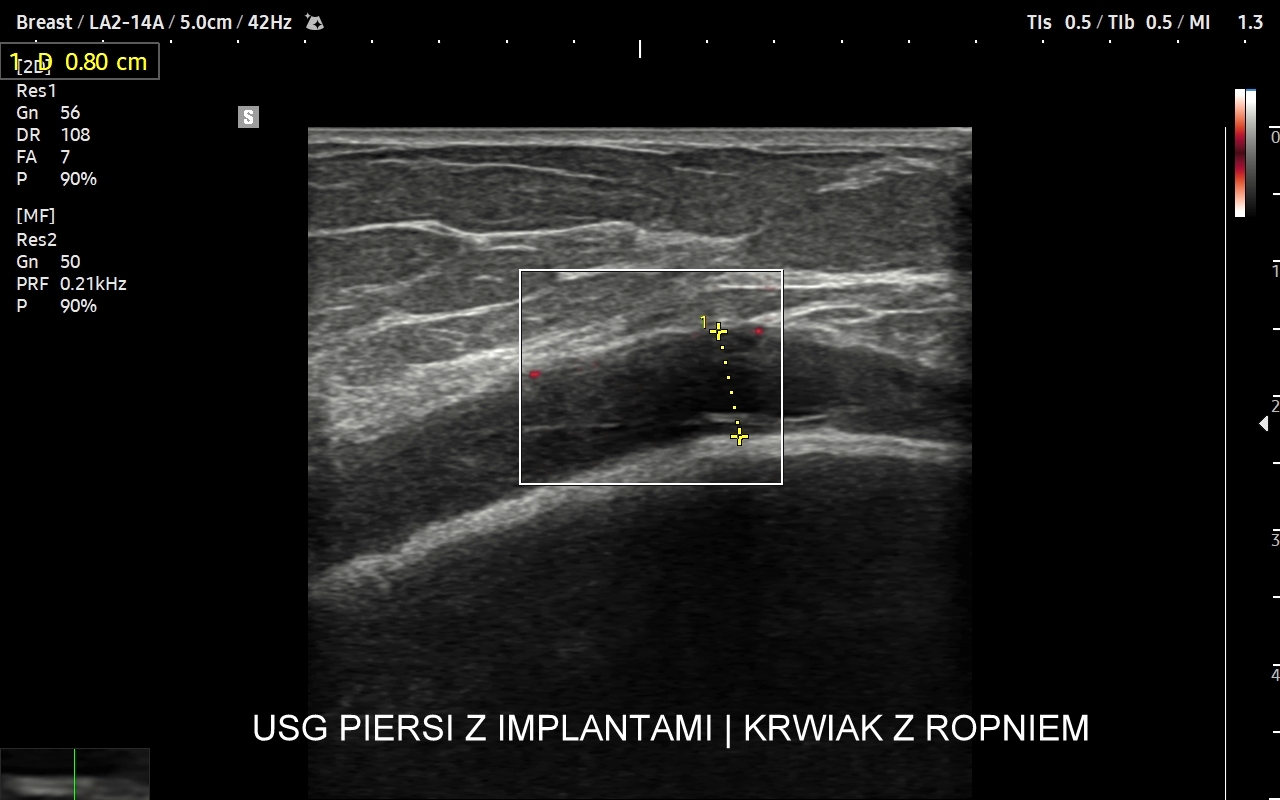

USG piersi z implantami

Badanie USG piersi z implantami jest szczególną procedurą diagnostyczną. Przeprowadza się ze wskazań wcześniej opisanych, jak w przypadku piersi bez implantów, ale także w schorzeniach ściśle związanych z implantem. Przykładami są powikłania chirurgiczne takie jak przemieszczenie się implantu, krwiak, ropne zapalenie tkanek wokół implantu, jego pęknięcie, a także wystąpienie chłoniaka BIA-ALCL (ang. breast implant associated anaplastic large cell lymphoma) jako odległego powikłania wszczepienia implantu piersi.